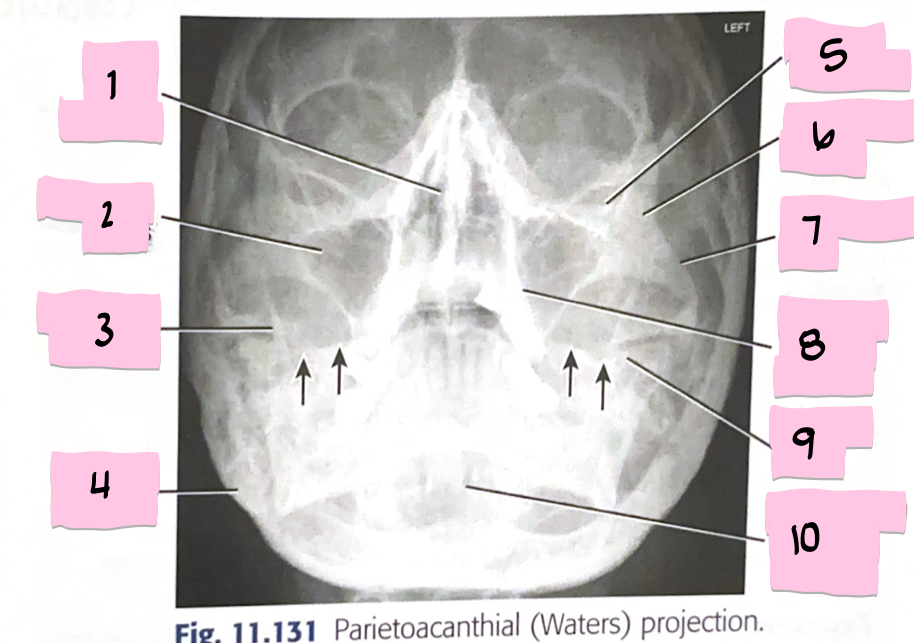

What is 1 pointing to?

Nasal bone

What is 2 pointing to?

Lacrimal bone

What is 3 pointing to?

Zygomatic bone

What is 4 pointing to?

Inferior nasal conchae

What is 5 pointing to?

Vomer

What is 6 pointing to?

Maxilla

What is 7 pointing to?

Mandible